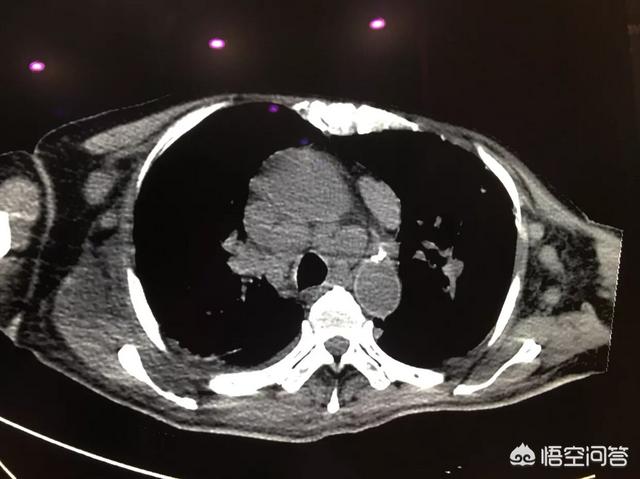

病例三,24岁年轻男性,也是摸到颈部无痛性包块就诊的。确诊淋巴瘤。淋巴瘤对化疗敏感,经过一个疗程化疗后,淋巴瘤明显缩小,如下图。随后的复查未见复发。但是不可掉以轻心,要坚持复查,因为还有可能复发。